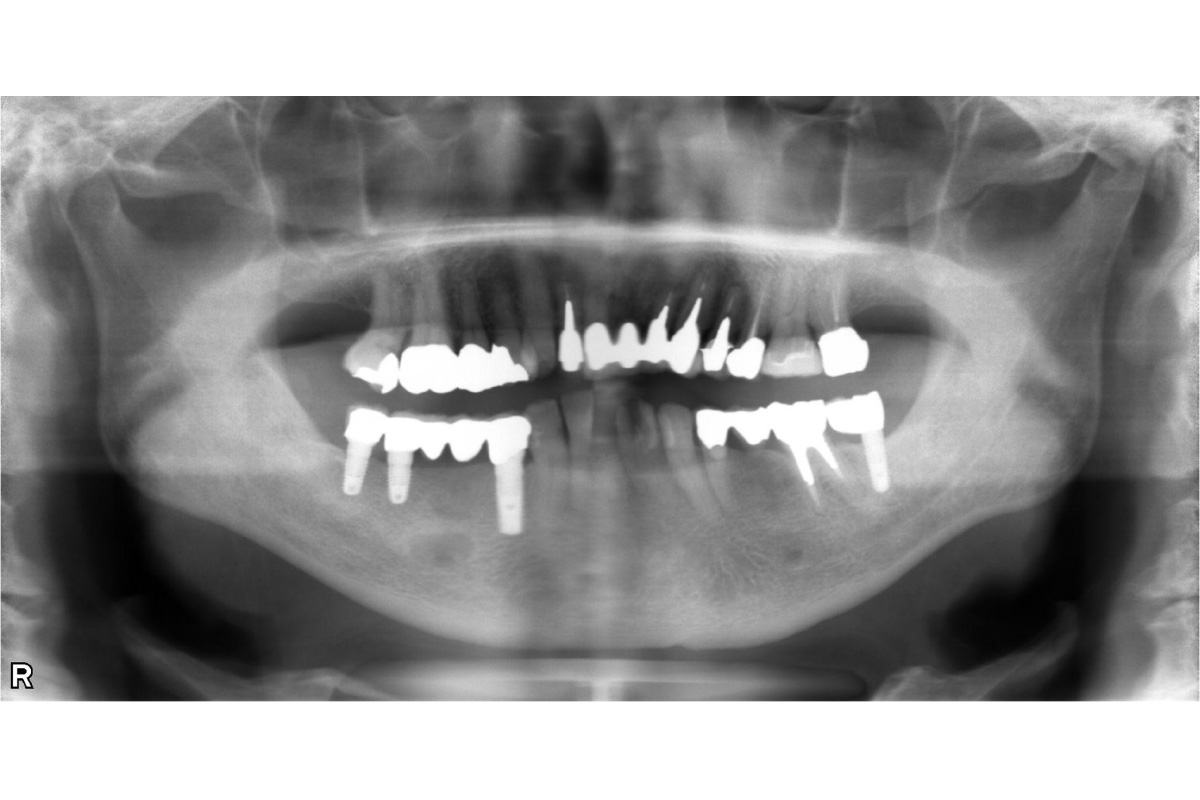

インプラント治療審美歯科 ジルコニアクラウン前歯をキレイにしたい骨造成 2026.03.12 前歯の抜歯が必要となった。隣の歯も含めてキレイに治したい。 治療前 治療後 治療前 インプラント 治療後 担当医 小林 健一 先生 主訴 前歯の抜歯が必要となった。 隣の歯も含めてキレイに治したい。 期間 6ヵ月 費用 1,179,200円(治療時) 治療内容 ジルコニアクラウン3本 インプラント治療2本 骨造成 治療に伴うリスク 外科処置を伴う 関連症例 インプラント治療 左下の奥歯を入れ歯以外で治したい 担当医 小林 健一 先生 主訴 左下の奥歯を入れ歯以外で治したい 期間 6ヵ月 費用 1,152,800円(治療時) 治療内容 抜歯・骨造成 インプラント治療 治療に伴うリスク 外科処置を伴う 2026-03-11 奥歯のインプラント骨造成 インプラント治療 下顎の入れ歯の安定が悪い。美味しい食事を取りたい。 担当医 小林 健一 先生 主訴 下顎の入れ歯の安定が悪い。美味しい食事を取りたい。 期間 5ヵ月 費用 2,457,400円(治療時) 治療内容 インプラント治療(フラップレス手術) 治療に伴うリスク 外科処置を伴う 2026-03-11 しっかり噛めるようになりたい入れ歯が合わない インプラント治療 左上の前歯が折れた。インプラントで治したい。 担当医 小林 健一 先生 主訴 左上の前歯が折れた。インプラントで治したい。 期間 4ヵ月 費用 628,650円(治療時) 治療内容 インプラント治療(抜歯即時埋入) 骨造成 結合組織移植術 治療に伴うリスク 外科処置を伴う 2026-03-23 前歯が折れた抜歯即時インプラント結合組織移植術骨造成 インプラント治療 前歯が折れた。抜歯はいいが、残りの歯を削らずにインプラントで治したい。 担当医 小林 健一 先生 主訴 前歯が折れた。抜歯はいいが、残りの歯を削らずにインプラントで治したい。 期間 5ヵ月 費用 686,400円(治療時) 治療内容 インプラント(抜歯即時埋入) 骨造成 カスタムアバットメント作成 治療に伴うリスク 外科処置を伴う 2026-03-11 歯が折れた骨造成 インプラント治療 上顎の歯をキレイに治したい。治療費を抑えたい。 担当医 小林 健一 先生 主訴 上顎の歯をキレイに治したい。治療費を抑えたい。 期間 費用 2,500,000円(治療時) 治療内容 仮歯 インプラント補綴(オールオン4) 静脈内鎮静法 治療に伴うリスク 外科処置を伴う 2026-03-11 オールオン4上顎の歯をキレイに治したい治療費を抑えたい インプラント治療 抜歯となった。インプラントで治したい。 担当医 小林 健一 先生 主訴 抜歯となった。インプラントで治したい。 期間 4ヵ月 費用 455,950円(治療時) 治療内容 インプラント治療(抜歯即時埋入) 骨造成 治療に伴うリスク 外科処置を伴う 2026-03-11 抜歯即時インプラント骨造成 インプラント治療 左下の歯を入れ歯以外で治したい。前歯のブリッジはそのままで治したい。 担当医 小林 健一 先生 主訴 左下の歯を入れ歯以外で治したい。前歯のブリッジはそのままで治したい。 期間 5ヵ月 費用 566,500円(治療時) 治療内容 骨造成 結合組織移植術 インプラント治療 治療に伴うリスク 外科処置を伴う 2026-03-11 結合組織移植術骨造成 インプラント治療審美歯科 前歯をインプラントで治したい。両隣の歯も揃えてキレイにしたい。 担当医 小林 健一 先生 主訴 前歯をインプラントで治したい。両隣の歯も揃えてキレイにしたい。 期間 4ヵ月 費用 899,800円(治療時) 治療内容 右上中切歯へのインプラント治療 (骨造成、結合組織移植) 両隣在歯のジルコニアクラウン 治療に伴うリスク 外科処置を伴う 2026-03-11 ジルコニアクラウン両隣の歯も揃えたい結合組織移植術骨造成